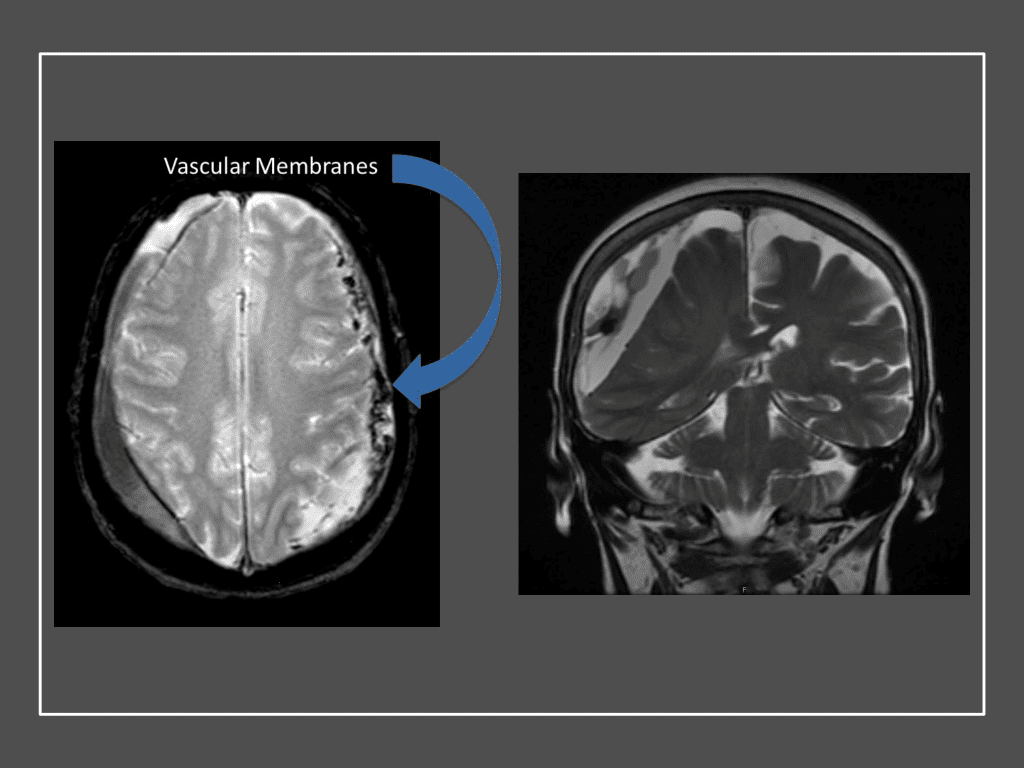

Figure 7. Neovascularized membranes within cSDH

Although conventional surgical methods, such as burr hole irrigation or observation in asymptomatic or minimally symptomatic patients have been the mainstay of treatment, middle meningeal artery (MMA) embolization has emerged as a promising adjunctive or alternative treatment. MMA embolization is a neuroendovascular technique which involves placing a microcatheter into the Middle Meningeal Artery, most commonly on the side of the cSDH (occasionally, bilateral embolization has been recommended for larger or bilateral collection. Embolization of both the anterior (frontal) and posterior (parietal) division is performed using a variety of embolic materials (liquid NBCA, Onyx, coils), although polyvinyl alcohol particles of <250 microns are most commonly used to achieve distal penetration and occlusion of the pre-capillary and capillary beds. The micro-leakage of blood and transudative proteinaceous inflammatory fluid in these inflammatory membranes is creating an imbalance in cycle of resorption and preventing resolution or promoting recurrence or growth of these cSDH collections and associated mass effect and midline shift.

It has been hypothesized that leakage from these inflammatory neomembrane capillaries, secondary to highly permeable endothelial gap junctions and microtears of the fragile neovascularized vessels contribute to this growth “latency” period (Phase 2), followed by clinical presentation (Phase 3) when a patient presents with symptoms (often non-localizing) including headaches, mental status changes, weakness, paresthesias, dysarthria, gait abnormalities, nausea, vomiting, stroke, seizures (10-20%), coma (2-15%), and brain herniation (approx. 2%) reported in many series and reviews. Risk factors that may be associated with and contribute to cSDH formation, growth, or recurrence include falls, antiplatelet or anticoagulation usage (10-30%), underlying systemic disease (i.e. Hepatic, Renal, Coagulaopathies), epilepsy, male gender, elderly age, and alcohol usage. 1,2,3,4